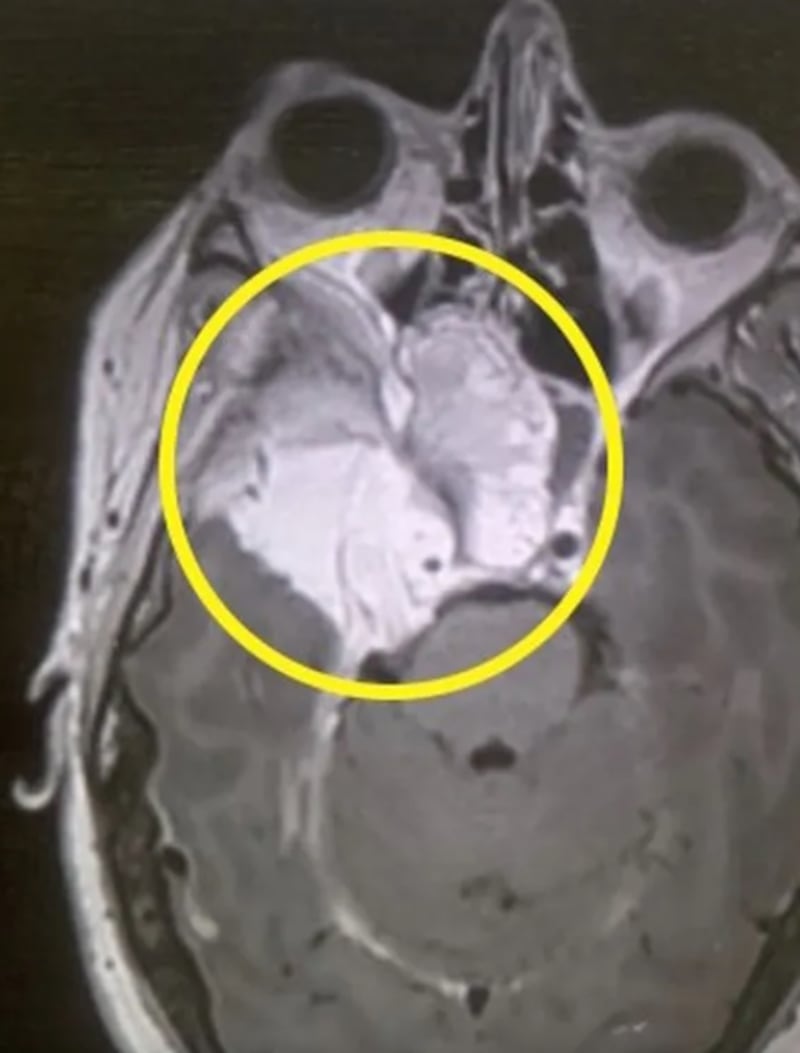

Durante la evaluación, los especialistas detectaron una anomalía en la parte posterior de su ojo derecho, lo que derivó en una remisión médica urgente. Una resonancia magnética confirmó la presencia de un meningioma, un tipo de tumor cerebral que en la mayoría de los casos es benigno.